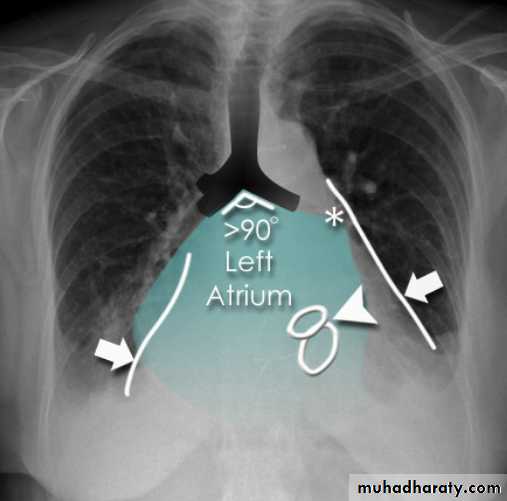

Mitral valve disease

Radiographic features

Plain film

Typical radiographic features of mitral regurgitation include :

frontal projection

1.left atrial enlargement

convexity or straightening of the left atrial appendage just below the main pulmonary artery (along left heart border)

2.double density sign: the right side of the enlarged left atrium pushes into the adjacent lung and creates an addition contour superimposed over the right heart

3.elevation of the left main bronchus and splaying of the carina

4.upper zone venous enlargement due to pulmonary venous hypertension

5.left ventricular enlargement is also eventually present due to volume overload

6.Features of pulmonary edema may also be present.